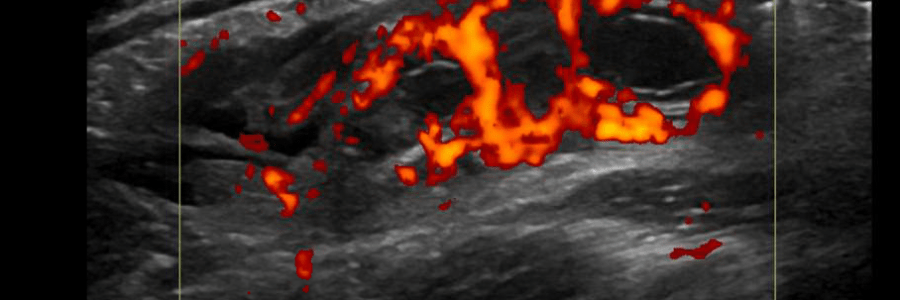

Intestinal Malrotation (Mid Gut Volvulus)

Intestinal malrotation due to the cessation of normal intestinal rotation in the fetus. The gastrointestinal tract divides into the foregut, midgut, and hindgut. The small and large intestines undergo rapid growth during weeks four and five of development. [1] It is theorized that the intestines outgrow the space in the abdominal cavity causing them to… Read More Intestinal Malrotation (Mid Gut Volvulus)